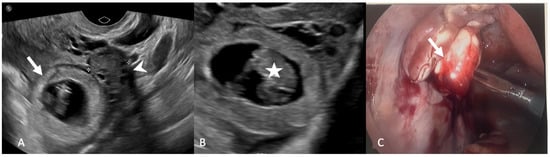

5.1.3. Adnexal Ectopic Pregnancy

5.1.4. Adnexal Torsion